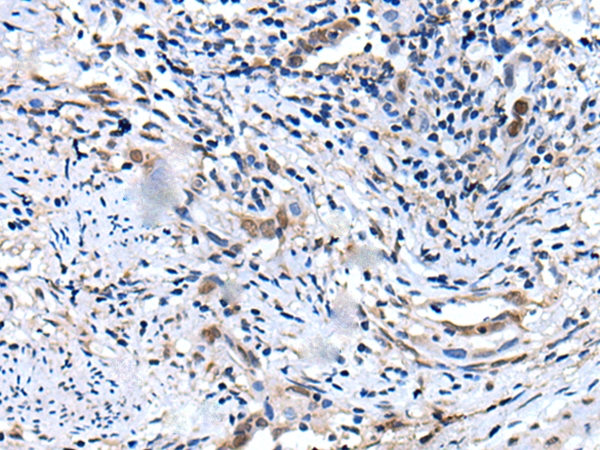

分类: 科研抗体货号: P02198别名: CILD18; HEATR2应用: IHC反应种属: Human